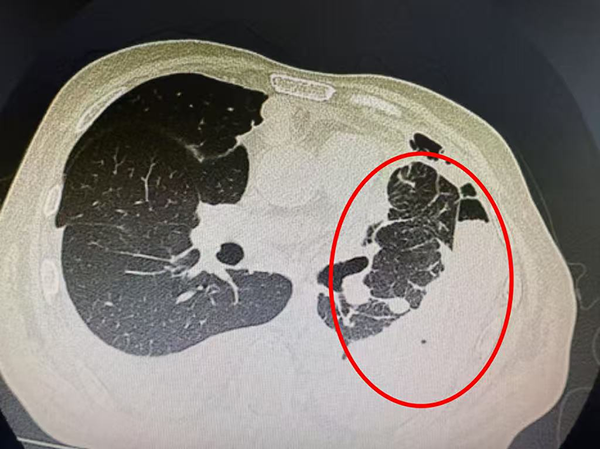

他来到市五院肿瘤内三科时,气短症状已十分严重,左肺完全压缩,纵膈明显右偏,“那段时间就像被困在深水里,连睡觉都要保持半坐姿,稍微平躺就感觉要窒息。”李先生回忆道。

图片1.png

入院时双肺CT